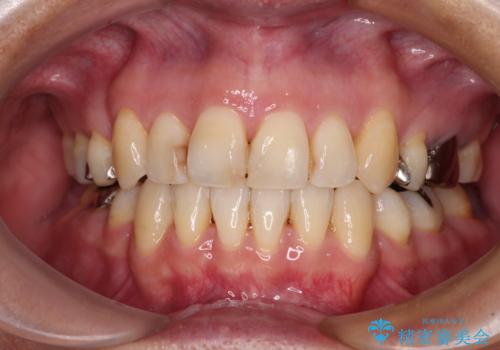

下の歯が前に出てしまう咬み合わせを治したい インビザラインによる矯正治療

- 前歯のクロスバイトを気にして来院された患者様です。

骨格的に下顎が前方位ではありますが、歯並びが改善されれば正常咬合となることが分かったため、インビザラインを用いて咬み合わせを改善していくこととしました。